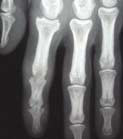

Le tableau clinique typique est constitué, chez une personne atteinte de psoriasis, par la survenue de douleurs articulaires d’horaire inflammatoire, révélant des arthrites périphériques, de forme oligoarticulaires et asymétriques le plus souvent, et pouvant atteindre les articulations interphalangiennes distales (fig. 1 et 2). Les manifestations cutanées du RP comprennent le psoriasis (généralement psoriasis en plaques) et le psoriasis unguéal, souvent marqué par un épaississement de l’ongle ressemblant à une mycose.

Dans les formes oligoarticulaires, on peut traiter avec un traitement symptomatique seul. Cependant, chez les patients atteints de forme polyarticulaire (plus de quatre synovites) ou présentant une maladie mono- ou oligo-articulaire mais avec des facteurs de mauvais pronostic (atteinte structurale à la radiographie, syndrome inflammatoire biologique, présence de dactylite ou d’atteinte des ongles), il est recommandé de commencer directement ou très rapidement un traitement de fond.6,7